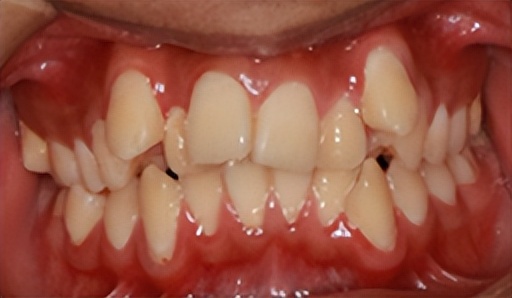

需拔牙矫治的牙齿拥挤病例

现代人随着食物精细程度的增加,咀嚼运动不断减少,咀嚼肌肉退化,颌骨也变小,没有足够的空间容纳所有的牙齿,易造成牙齿的错位拥挤。

再加上东方人面型的特点,大约有60%-70%的人群需要通过拔牙来提供空间排齐牙列,内收前牙,改善侧貌。